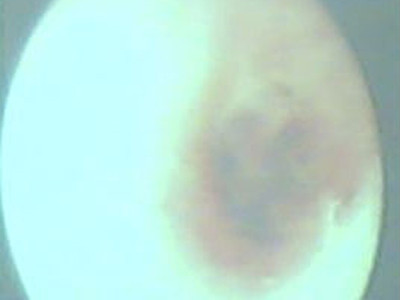

| Tổ kiến nằm gọn trong tai phải của cô bé. Ảnh: Chilli. |

Bác sĩ Hung Yuan-Tsung, trưởng khoa Tai – Mũi - Họng bệnh viện Đài Bắc cho biết, hơn 20 con kiến đang làm tổ trong tai phải của nữ bệnh nhân 16 tuổi. Ngoài ra, còn có vài con kiến nữa cũng “đi dạo” trong tai trái của bệnh nhân này.